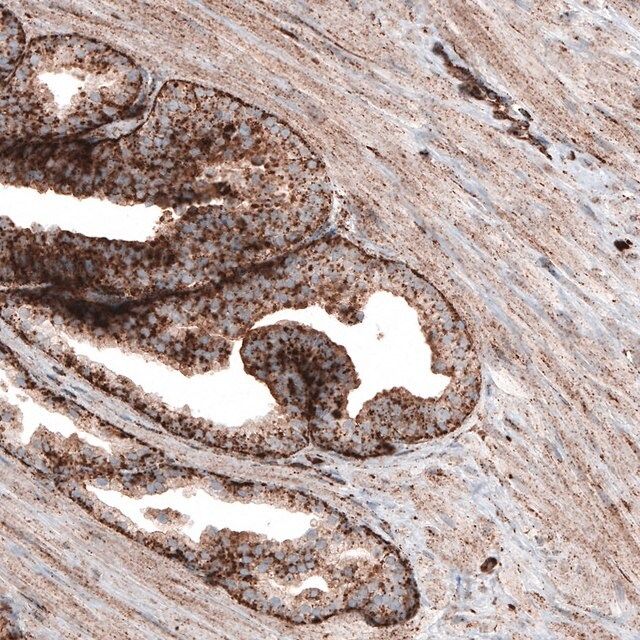

Lysosomal associated membrane protein 1

- IHC tissue array of 44 normal human tissues and 20 of the most common cancer type tissues.

| technique(s) | immunoblotting: 1 μg/mL immunohistochemistry: 1:1000-1:2500 |